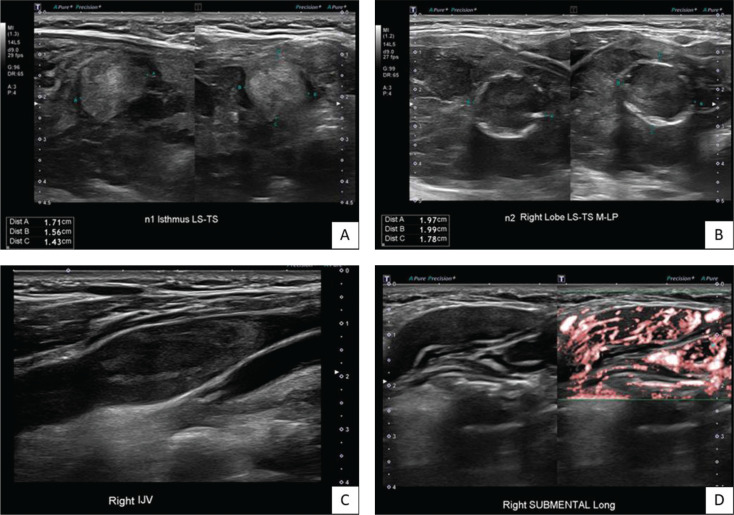

We report a case of an uncommonly aggressive presentation of the rare entity of synchronous papillary (PTC) and follicular thyroid carcinomas (FTC) in a 67-year-old female initially presenting with thyrotoxicosis from Graves' disease. She was found to have two thyroid nodules with extensive intra-cardiac tumour thrombus, symptomatic left pelvis bony metastasis with pathological fracture, pulmonary metastases and mediastinal lymph node metastases. Further investigations suggested a diagnosis of synchronous papillary and metastatic follicular thyroid cancer. Treatment with radical surgery followed by adjuvant therapeutic radioiodine ablation was proposed, but the patient declined all forms of cancer-specific therapy and was elected solely for a palliative approach to treatment. We discuss the diagnostic considerations in arriving at the diagnosis of synchronous thyroid malignancy - in this case the clear features of PTC and the strong probability of FTC due to invasiveness and metastatic follicular lesions. This case underscores potential limitations of the ACR TI-RADS system, notably with certain ultrasonographic features suggesting malignancy that might not be adequately captured. Notably, the aggressive presentation of DTC in this case may be contributed by the concurrent presence of Graves' Disease, suggesting heightened vigilance when assessing potential thyroid malignancies in such patients.